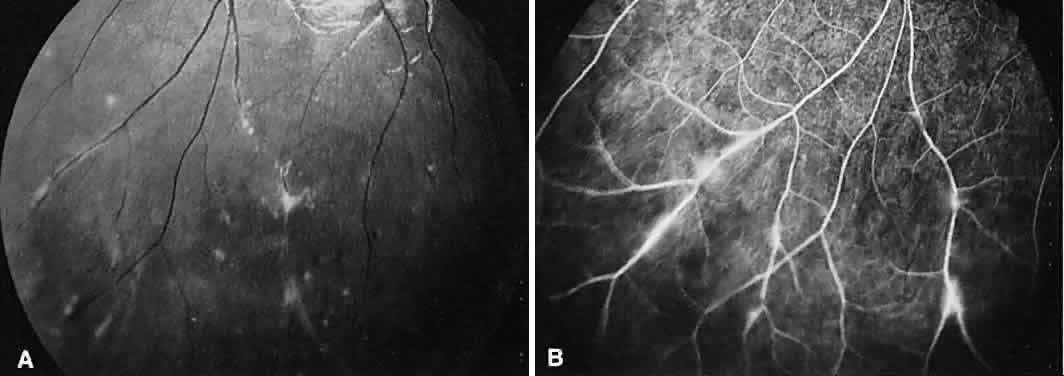

TUBERCULOSIS

Tuberculosis has numerous ocular presentations, including anterior uveitis, scleritis, sclerokeratitis, phlyctenulosis, interstitial keratitis, choroidal granulomas (often with serous elevations; Fig. 23A),retinal exudate, macular star formation, retinal vas-culitis, vitreous cells, SRNV, and optic nerve granulomas. Eales' disease, a bilateral peripheral vasculitis with peripheral neovascularization and vitreous hemorrhage, frequently occurs in young men who have positive purified protein derivative test results (Fig. 24).

Fig. 24. Eales' disease (retinal vasculitis). A. Angiography of the left disc shows staining of the retinal vessels, particularly the venules in the late venous stage. B. In the far periphery, there is staining of the peripheral vessels (particularly venules) just adjacent to an area of nonperfused retina. The hypofluorescent areas represent intraretinal hemorrhages.

On fluorescein angiography, a choroidal tuberculoma hyperfluoresces in the late phase (see Fig. 23B). There may be leakage and pooling of dye if there is a serous retinal detachment. As the tuberculoma responds to therapy, the hyperfluorescence decreases and pockets of hypofluorescence can be seen.79 Retinal arteriovenous shunts with dilated capillaries also can be seen in the granuloma.80 Peri-phlebitis causes capillary dropout and venous staining. Neovascularization of the peripheral retina is not uncommon.